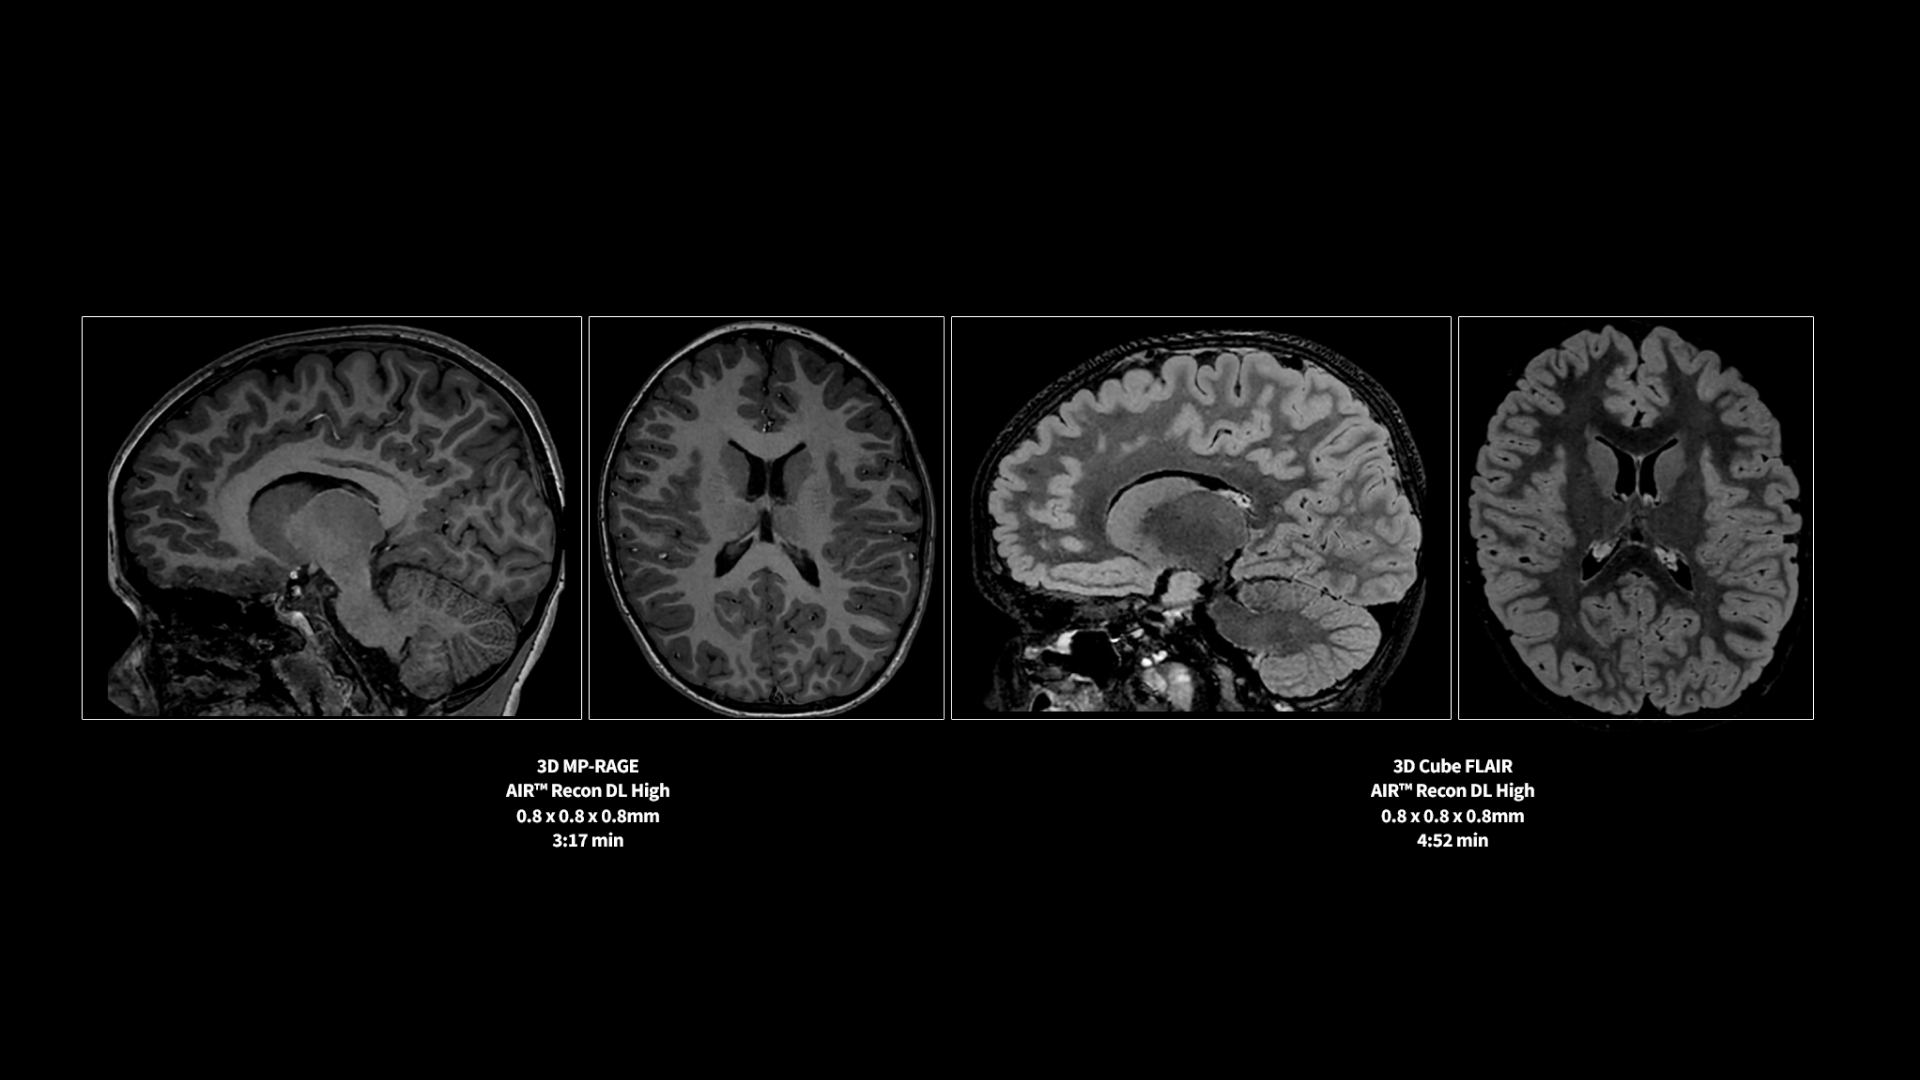

Revolutionary, deep-learning-based reconstruction techniques such as AIR™ Recon DL provide sharper, clearer, and accurate images

Pin-sharp image quality and exceptional speed with AIR™ Recon DL and Sonic™ DL​

SIGNA™ Premier offers the versatility you need to fulfill all your clinical needs. Explore the advanced imaging and clinical capabilities achievable with the SIGNA™ Premier system.

Experience pin-sharp precision and remarkable speed with a 3T SIGNA™ Premier MRI scanner, coupled with AIR™ Recon DL and Sonic™ DL.